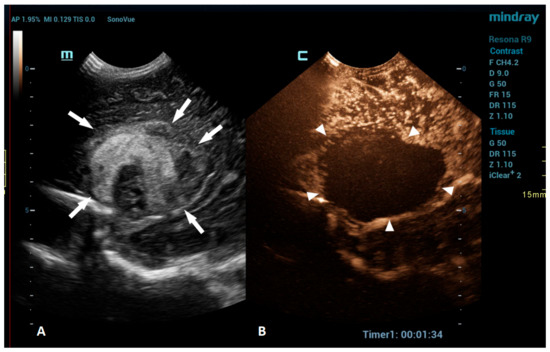

An intracranial hemorrhage (ICH) in the neonatal period is a serious clinical problem and an important cause of morbidity and mortality [52]. Many inherited and acquired disorders may cause a neonatal ICH. However, in a large proportion of cases, the etiology cannot be identified [53]. Full-term neonates with an ICH commonly present with clinical features, such as apnea, bradycardia, and seizures [54,55,56]. With improvements in diagnostic imaging in recent years, even a small ICH is being increasingly recognized. The true incidence of ICHs is likely higher than reported, as only a fraction of infants with an ICH present with clinical features [54]. Diagnostic imaging plays an important role in the detection of ICHs. A cranial US is a first-line modality for the evaluation of a neonate suspected of having an ICH. USs are a highly sensitive and dependable tool for assessing the ventricular system and central brain structures. It is highly effective in detecting germinal matrix hemorrhages, intraventricular hemorrhages, and hemorrhages in central brain structures [53]. However, a limitation of the US is its poor visualization of the peripheral and deep brain regions. Using additional acoustic windows, like the mastoid fontanelle, posterior fontanelle, or foramen magnum, can help overcome these limitations. In cases where more detailed information about ICH lesions is necessary, or if there are still suspicions despite there being normal cranial US results, MRI is the preferred imaging method. Unlike USs, MRI can capture images of the entire brain, as it is not limited by acoustic windows. Furthermore, MRI has the ability to utilize hemorrhage-sensitive sequences like susceptibility-weighted imaging (SWI), which is unparalleled in its sensitivity in detecting hemorrhages [57]. Therefore, MRI is considered the gold standard for further imaging when more comprehensive information is needed. However, there are also limitations to the use of MRI. In the neonatal period, MRI typically requires general anesthesia. Additionally, patients with a suspected ICH are often located in the neonatal intensive care unit, and they may be difficult to move to an MRI machine in another department; therefore, MRI is not always feasible. A CEUS is an emerging radiological modality that could prove especially useful in the detection of ICHs. The CEUS is a technique based on the vascularity and perfusion of the observed organ. As such, it may be an ideal tool to detect areas without perfusion, such as hemorrhages. The areas with normal perfusion greatly differ in terms of signal from that of the areas without perfusion, which should also improve the visualization of such areas in the peripheral and deep regions of the brain. Several recent studies have already described cases of ICHs that were more accurately diagnosed using CEUSs in comparison to that using MRI [20,51]. CEUS shows preserved cerebral perfusion around the hemorrhage (i.e., the presence of microbubbles within the brain) and the region of heterogeneous hypoperfusion in the affected area of the brain with the hypoechoic hemorrhagic core (i.e., no microbubbles entering the hematoma) (Figure 3).

Figure 3.

A 1-day-old boy who presented with apnea. (A) The sagittal grayscale ultrasound brain image reveals a heterogeneous lesion (arrows) in the right frontotemporal region. (B) The sagittal CEUS image confirms avascularity of the lesion (arrowheads), consistent with the hemorrhage, and no obvious vascular malformation.

CEUSs can also be a great problem-solving tool in the assessment of brain vasculature, especially the evaluation of brain sinuses for the presence of thrombosis. Due to the slow flow in the brain sinuses, MRI can be unreliable in diagnosing sinus thrombosis [74]. CEUSs using an approach through the anterior fontanelle enables a good visualization of the sagittal sinus, while the transtemporal and transmastoid approaches provide a great visualization of the transverse sinuses (Figure 5).

Figure 5.

A 5-day-old boy diagnosed with hypoxic-ischemic encephalopathy was investigated for suspected thrombosis of the right transverse sinus (suspected on MRI scan). (A) The transverse reference grayscale ultrasound image through the right mastoid fontanelle and increased echogenicity within the transverse sinus (arrow). (B) The CEUS image of the right transverse sinus shows the sinus with high signal intensity (arrow), ruling out thrombosis.